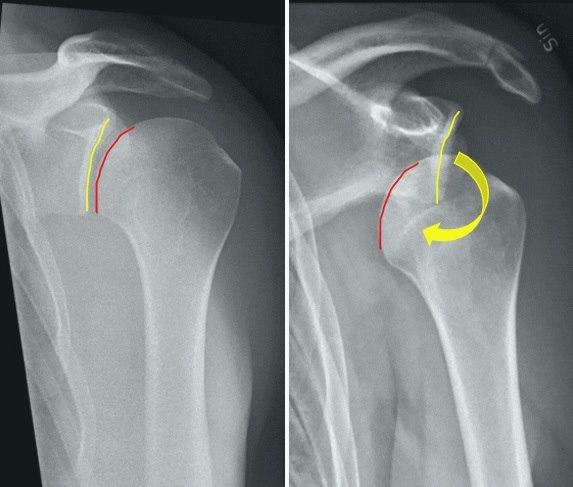

Luksasjon av skulderleddet betyr at skulderen er "ute av ledd". Skulderleddet dannes i møtepunktet mellom skulderbladet (scapula) og overarmsbeinet (humerus). Skulderbladet er leddskålen, og den beskytter godt mot forskyvninger av leddhodet oppover og bakover. Fremover derimot er det først og fremst muskler som hindrer at leddhodet forskyves, og det kan ved kraftige skader bli en for svak beskyttelse.

Fremre luksasjon er når hodet til overarmsbeinet ligger foran leddhulen i skulderbladet. Leddhodet kan skyves ut av leddskåla i flere retninger, men fremre luksasjon er den hyppigste formen for skulderluksasjon. Tilstanden skyldes oftest en skade (støt, slag, fall, voldsom bevegelse) som etterfølges av sterke smerter i skulderen. Den skadede har problemer med å bevege skulderen. 90-95 prosent av skulderluksasjonene er fremre luksasjoner, dvs. leddhodet glir opp på fremsiden av skulderleddet.